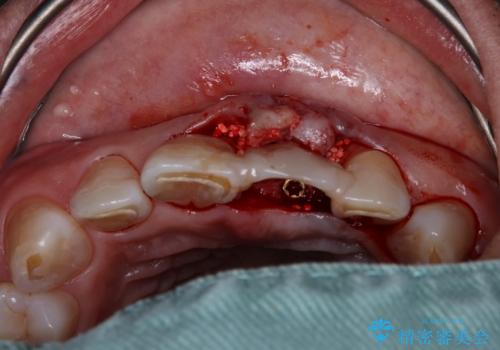

インプラント治療を希望されておりましたが、軟組織の欠損が非常に大きいため、骨の回復を待ちながら歯肉の形態を整えていくこととしました。

歯肉形態を概ね回復するタイミングでインプラントを埋入し、補綴治療を行うこととしました。

歯肉移植術による更なる歯肉ラインの改善も検討しましたが、笑ったときに歯肉ラインは唇に隠れてしまうため、現在の位置にて仕上げることとしました。

骨の前後幅が小さかったため、細いインプラントを選択せざるを得ない状況でした。咬合力が非常に強い方のため、就寝時のマウスピース装着を徹底していただき、インプラントへの負担を軽減することとしています。